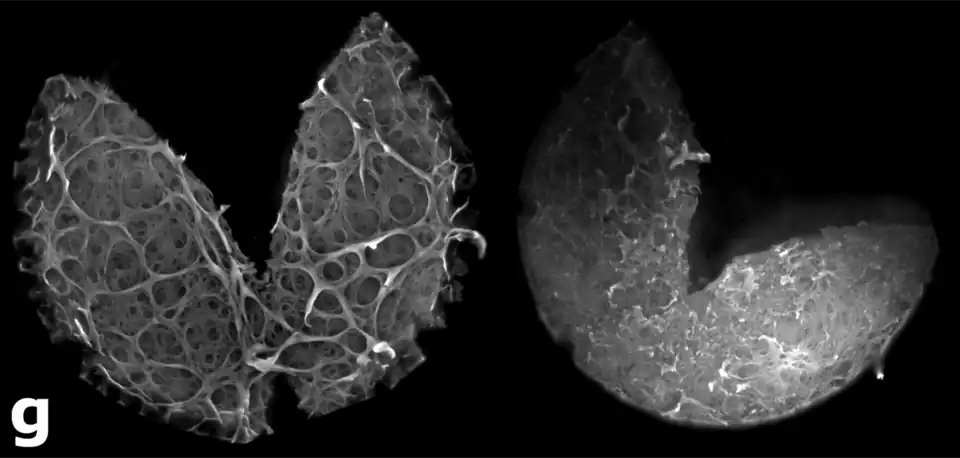

Durante el quinto día del desarrollo del embrión, la zona pelúcida se irá degenerando por medio de una serie de ciclos de expansión y contracción; como también por la acción de enzimas, para dar paso a la implantación. El blastocisto, a través de varios procesos debe deshacerse de la Zona pelúcida (ZP) antes de la implantación. Las anormalidades intrínsecas de la ZP, son uno de los factores que limitan la reproducción en los seres humanos.

Este fenómeno recibe el nombre de eclosión. El embrión en estado de blastocisto, al eclosionar de la zona pelúcida, se llamará embrión o blastocisto implantado.